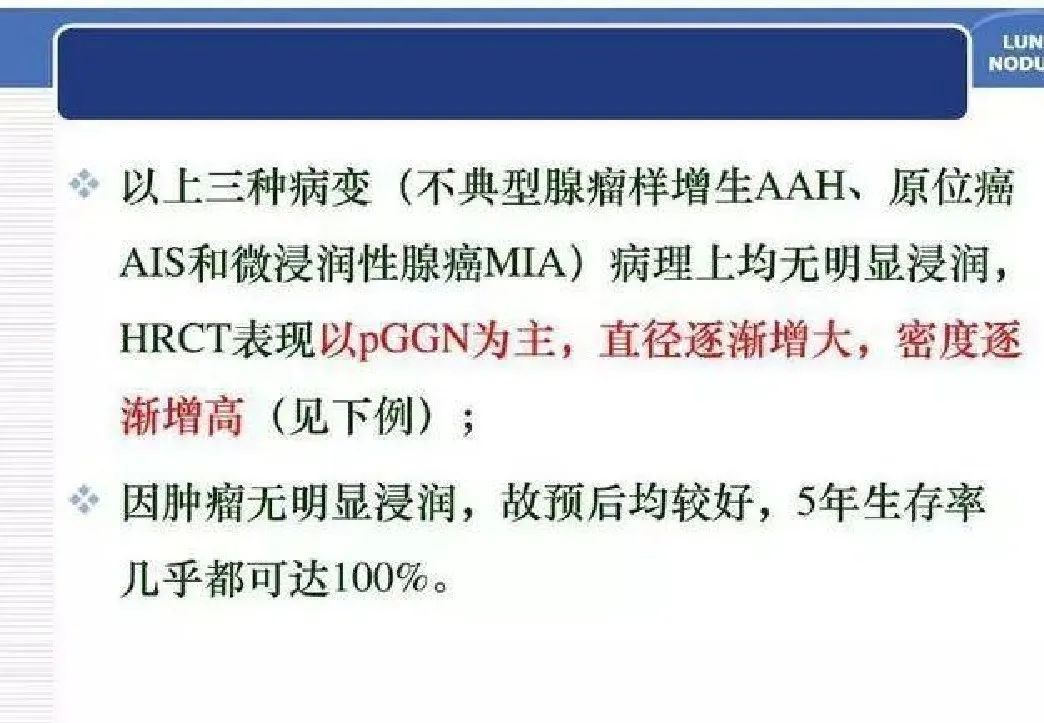

癌前病变 - 腺瘤样不典型增生(AAH)

原位癌(AIS)

微浸润腺癌(MIA)

当了解肺结节的演变过程后,我们发现,在发现肺结节时,不必过于慌张。事实上,90%以上的肺结节都是良性的,可能是由感染、炎症、肺部疾病或其他非癌性原因引起。当然,虽然大多数情况下肺结节是良性的,但由于肺癌的存在,发现肺结节时仍然需要谨慎对待。及早发现和评估肺结节的性质对于确定是否需要治疗至关重要。